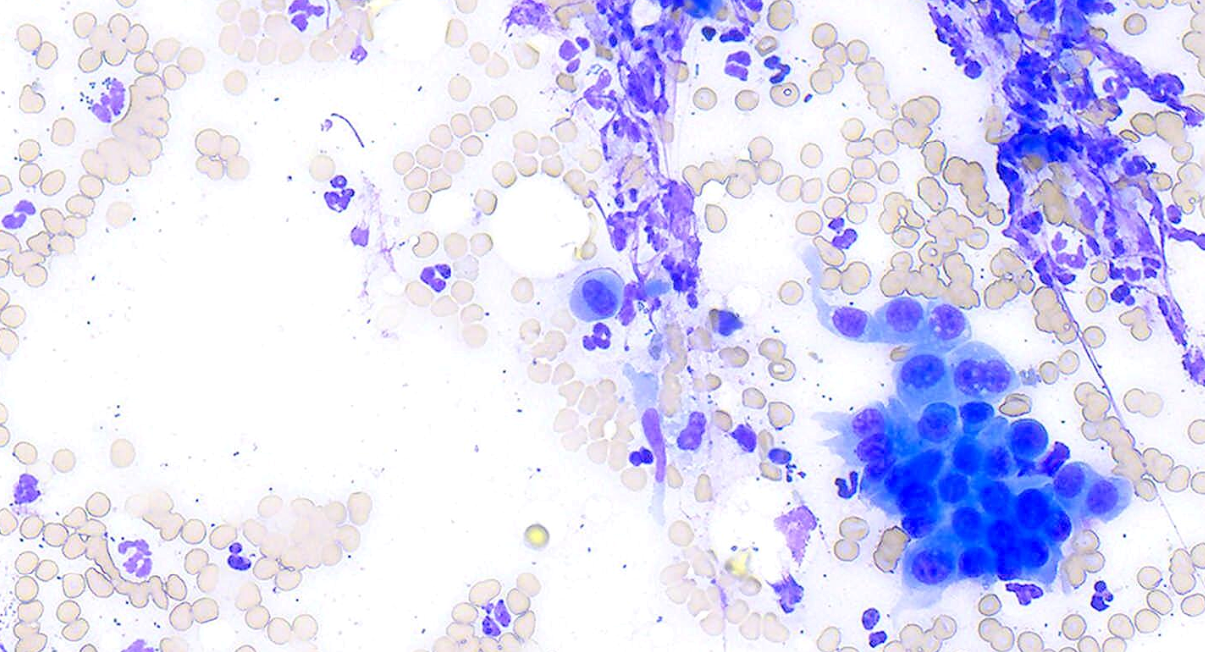

Below is an image of an aspirate of an enlarged prostate of a 12-year-old castrated male Chinese Crested dog. Which of the following are the most likely diagnoses? (You may select more than one option.)